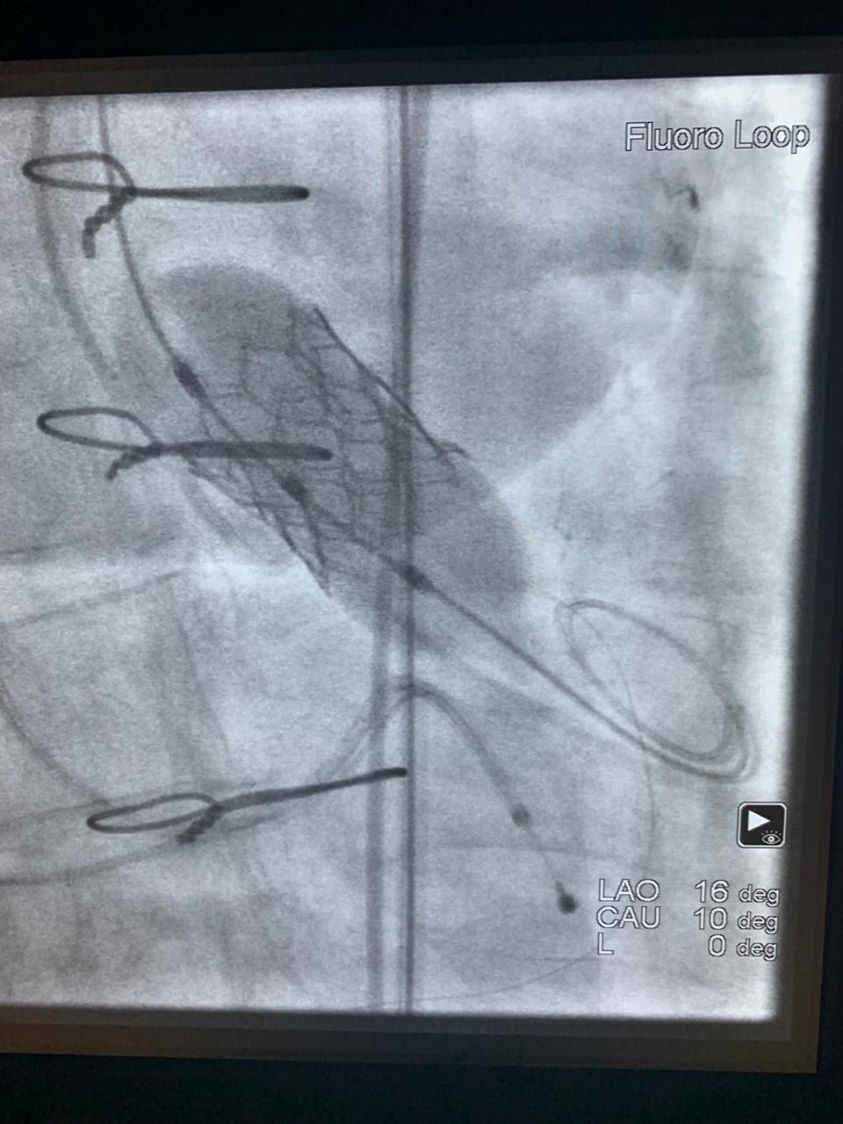

TAVI & TAVR